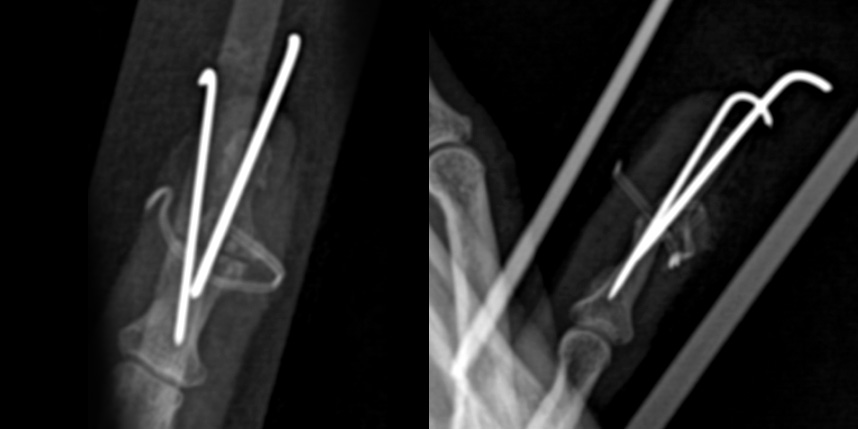

관절 유합술의 경우 “H” 절개를 통하여 관절을 충분히 노출시킨 후 관절 연골을 깨끗하게 제거하여 뼈와 뼈가 직접적으로 맞닿도록 한 후 이를 이용하여 고정합니다. 뼈 손상을 최소화하기 위하여 두 개의 K 강선으로 축고정과 회전고정을 하는 방식을 이용하며 6-8주 째 K 강선을 제거합니다.

관절 유합술의 경우 증상이 심한 중증 관절염이 대상이 되며, 관절을 영구적으로 굳히는 수술이기 때문에

통증은 사라지고 휘어졌던 손가락이 일자가 되지만 끝마디 굴곡이 불가능해집니다. 직업적인 필요에 따라 굽힌 상태로 굳힐 수도 있으나

원위지절의 경우 일반적으로 완전히 편 상태로 굳히게 됩니다. 사람마다 차이가 있으나 한, 두 손가락에 하는 경우

굳어 있는 것에 대한 불편감보다는 통증 완화로 인한 만족감이 훨씬 높습니다.